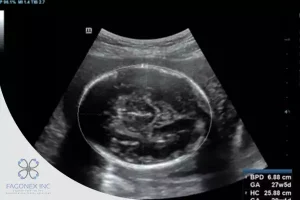

In prenatal ultrasound evaluations, OFD, or occipitofrontal diameter, is a critical fetal head measurement that helps healthcare professionals assess a baby’s development inside the womb. The OFD represents the distance between the occiput (back of the fetal skull) and the forehead (frontal bone). It is measured on an axial plane of the fetal head, usually taken during the second trimester or later.

Using high-resolution, portable devices like the Sono Mobile™️ CT61, sonographers and physicians can acquire accurate and real-time measurements of fetal biometry, including the OFD, during routine pregnancy scans. This parameter offers insight into fetal growth patterns, brain development, head shape, and potential abnormalities.

The OFD is typically measured in the transventricular plane, an axial slice through the fetal head where the midline falx, cavum septum pellucidum, and thalami are visible. The measurement is taken from the outer edge of the occipital bone to the outer edge of the frontal bone, using calipers aligned parallel to the midline.

With the portability and precision of devices like the Sono Mobile™️ CT61, clinicians can easily capture and analyze OFD during routine checkups, even in remote or point-of-care environments, ensuring that care is accessible and consistent.